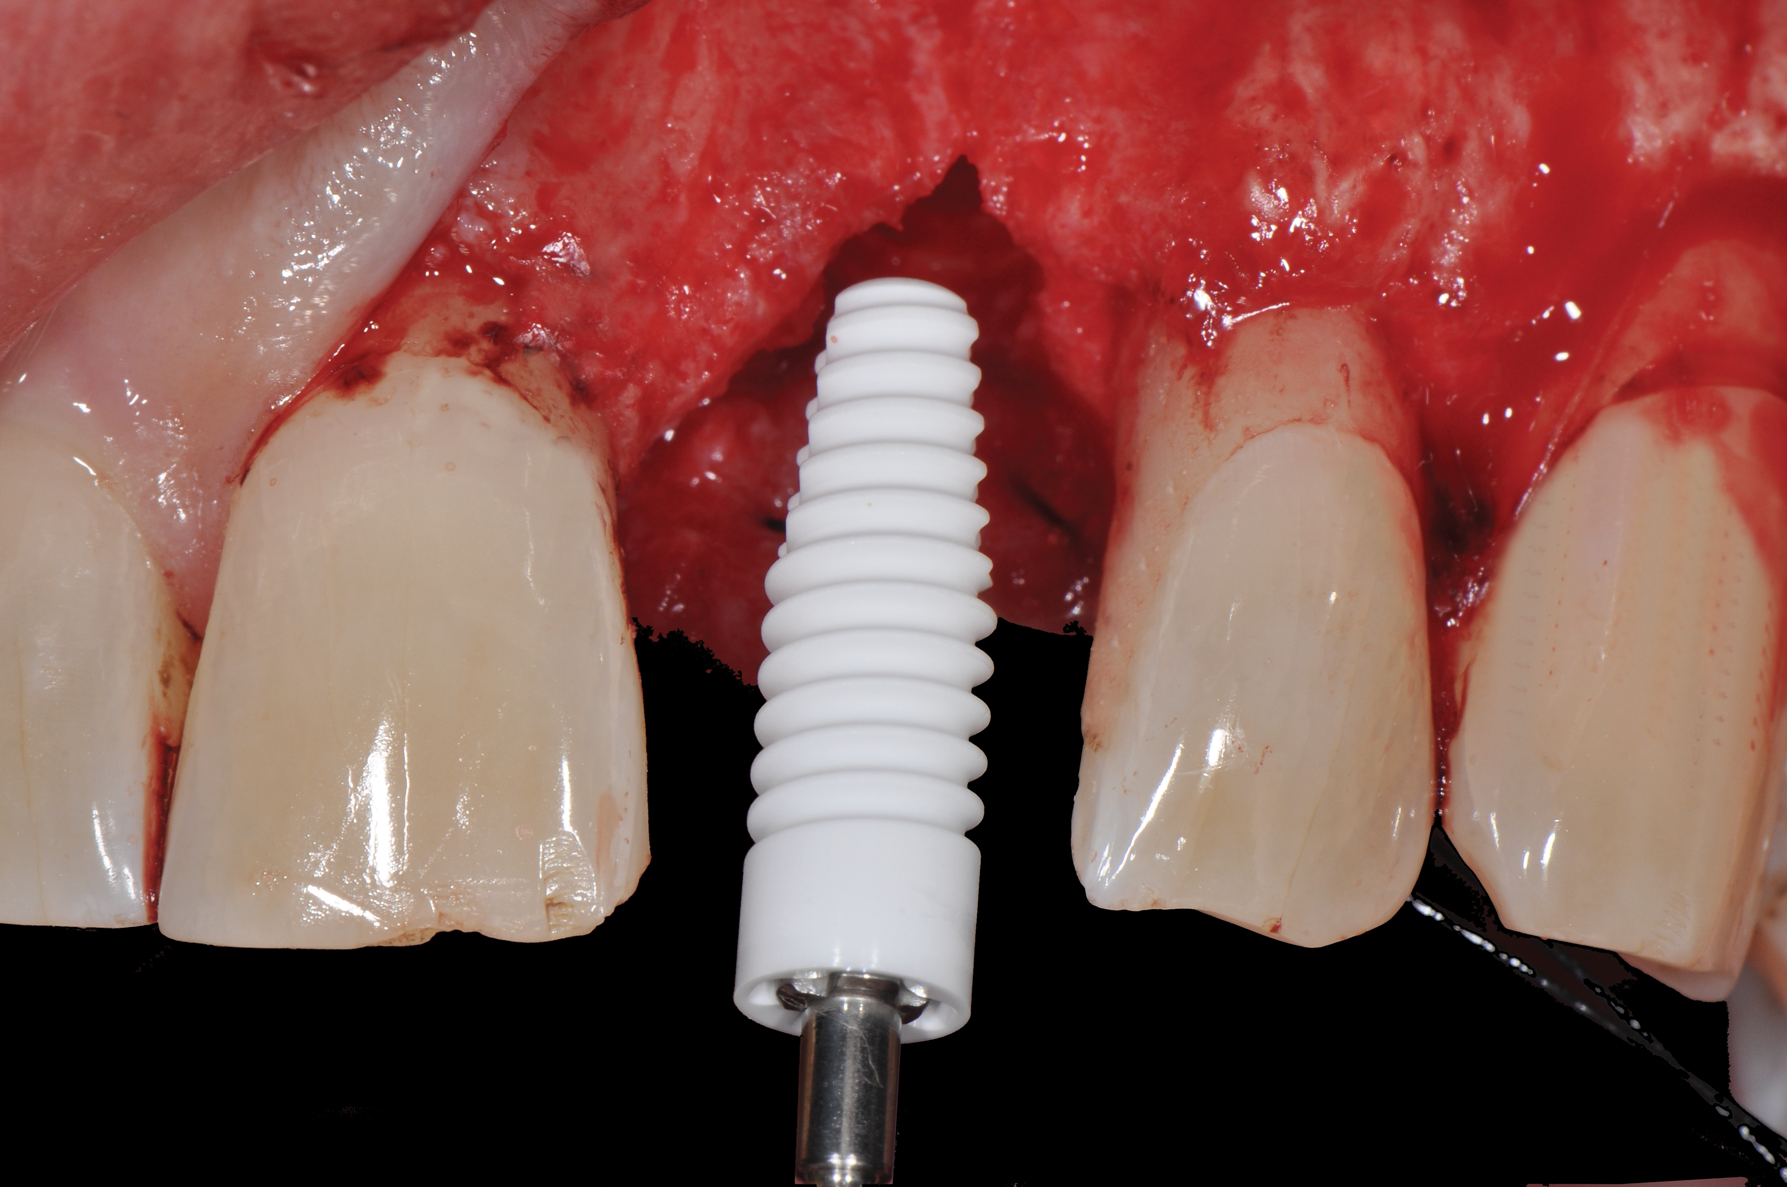

Fig 8. Insertion of metal-free ceramic implant (4.2 mm x 12 mm) 8 weeks after extraction of hopeless tooth No. 9.

Figure 8